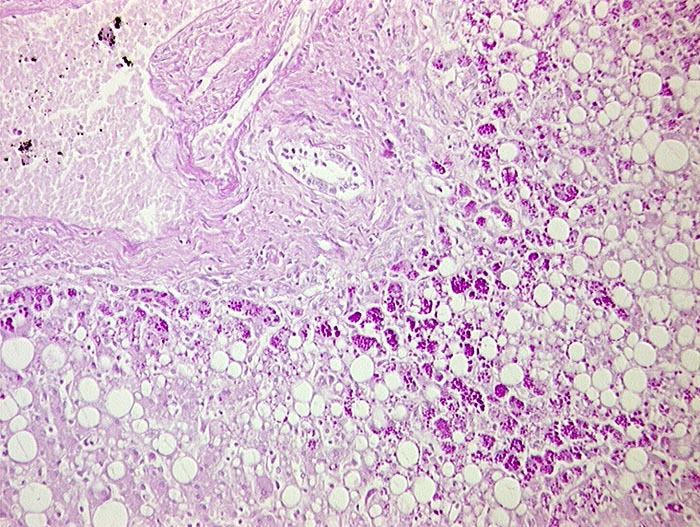

PathoPic ID 683 - alpha-1-Antitrypsinmangel

alpha-1-Antitrypsinmangel

Systemerkrankung/Immunpathologie

Leber

Leber, Gallenwege, Pankreas

PAS positive Einschlüsse in periportalen Hepatozyten.

Histologie